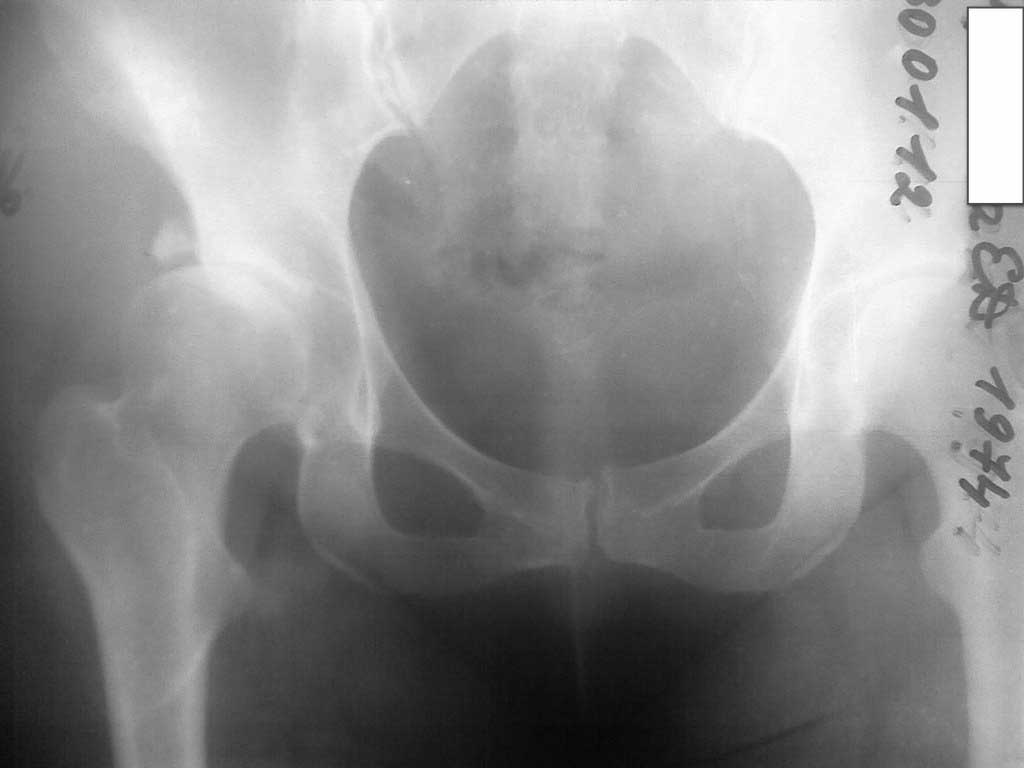

На лицо диспластический коксартроз. Очень хороший многолетний результат

дает периацетабулярная остеотомия по J. Matta.

> Женщина, медсестра отделения городской больницы хирургического профиля,

> 35лет, после родов 4 года назад стала отмечать боли в правом тазобедренном

> суставе. Ходит едва прихрамывая, хотя сама замечает, что хромает

> достаточно сильно.Были выполнены снимки, через 2 года РКТ(2010). На сегодня

> на рентгенограмме (в приложении) тазобедренного сустава свободный фрагмент

> крыши вертлужной впадины, сужение латеральной трети суставной щели.

> Травму категорически отрицает. Судить сегодня - что это - незамеченный

> перелом или вариант дисплазии трудно и с точки зрения здоровья сустава -

> бессмысленно.